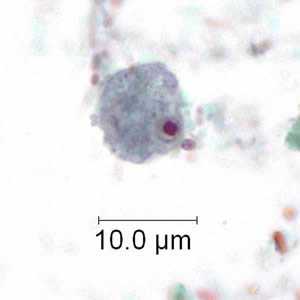

E. polecki trophozoites stained with trichrome.

Figure A: Trophozoite of E. polecki stained with trichrome.

Figure B: Trophozoite of E. polecki stained with trichrome.

Figure C: Trophozoite of E. polecki stained with trichrome.

Figure D: Trophozoite of E. polecki stained with trichrome.

Figure E: Trophozoite of E. polecki stained with trichrome.